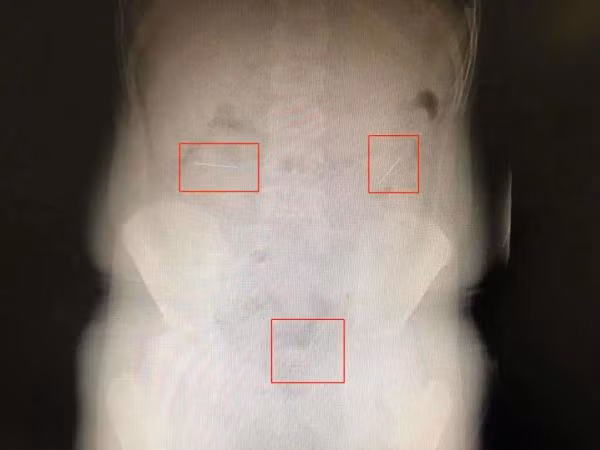

Nghe xong lời trần thuật của con trai, mẹ Lạc Lạc vội vã đưa cậu bé đến bệnh viện. Tại đây, sau khi chụp phim X-quang, các bác sĩ phát hiện phần bụng của Lạc Lạc có 4 "vật thể lạ" giống như kim tiêm.

Những cây kim này đi vào ruột non, qua đường tiêu hóa và đang di chuyển về phía ruột già. Ảnh: Theuntamed